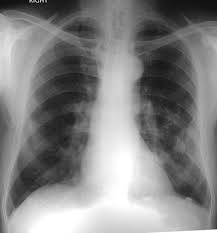

Asbestosis Pulmonary Disorders Msd Manual Professional Edition

Asbestosis Pulmonary Disorders Msd Manual Professional Edition from www.msdmanuals.com